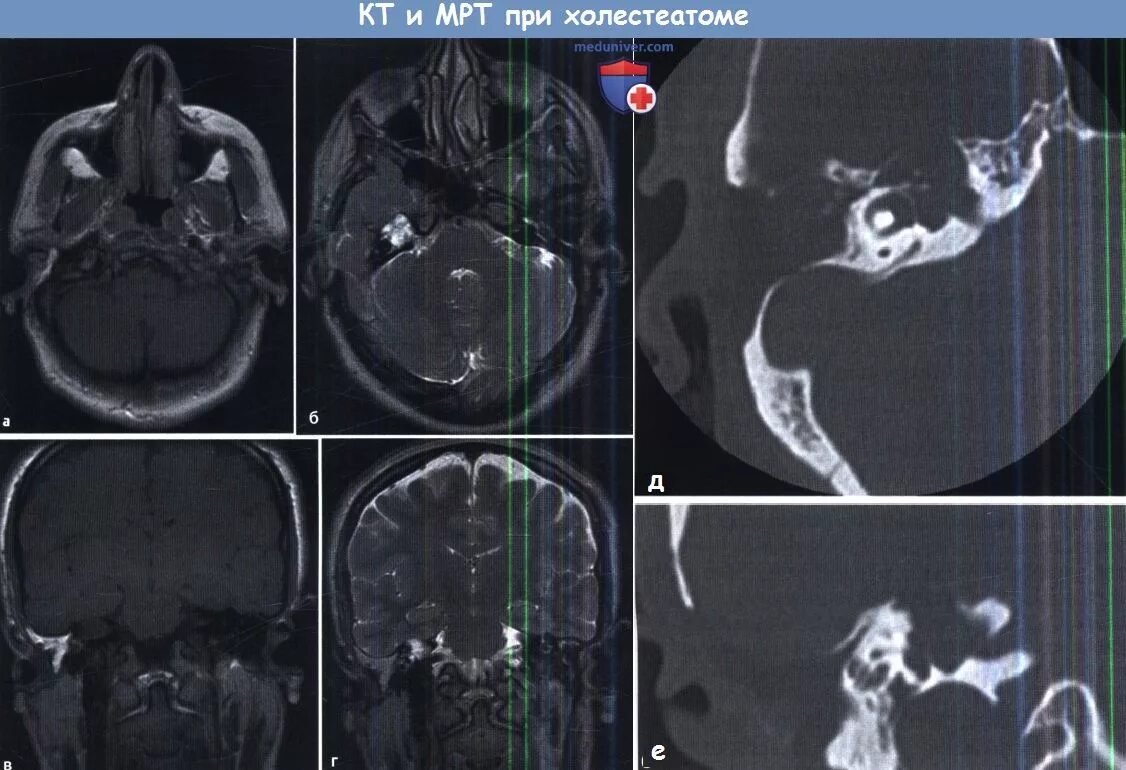

Мрт височных костей в режиме dwi